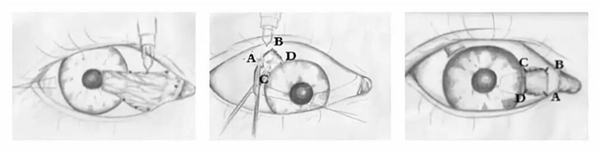

3.胬肉切除+自身结膜移植术

此种方法在切除胬肉病变后,在附近健康的角巩缘处取自身结膜作为植片,覆盖在已切除病变区域的巩膜上。

这种方式降低了翼状胬肉的术后复发的风险,能在切除翼状胬肉的同时,移植含有干细胞的健康结膜,有利于组织修复及防止翼状胬肉复发。

图(左):切除胬肉 图(中、右):移植含有干细胞的健康结膜